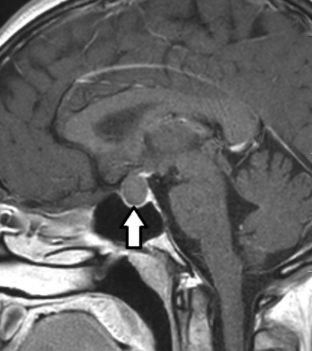

RM de cerebro, corte coronal ponderado en T2. En el lóbulo temporal derecho se observa una imagen quística simple (flecha). Corresponde a un quiste neuroglial.

Generalmente uniloculares, pueden sangrar o calcificar (►Fig. 5).8,9 Se producen por un remanente diverticular pineal o derivados de lesiones necro-hemorrágicas en la etapa embrionaria.9 En TC son hipodensos; en RM el 60% son iso o relativamente hiperintensos en ponderación T1 e hiperintensos en ponderación T2.4,8 El 60% realza en forma nodular o anular en forma irregular con gadolinio (►Fig. 5).8 El diagnóstico diferencial debe realizarse con:4,8

RM de cerebro, corte sagital ponderado en T1. La anatomía normal de la glándula pineal se encuentra modificada por la presencia de una imagen de apariencia quística simple (flecha).